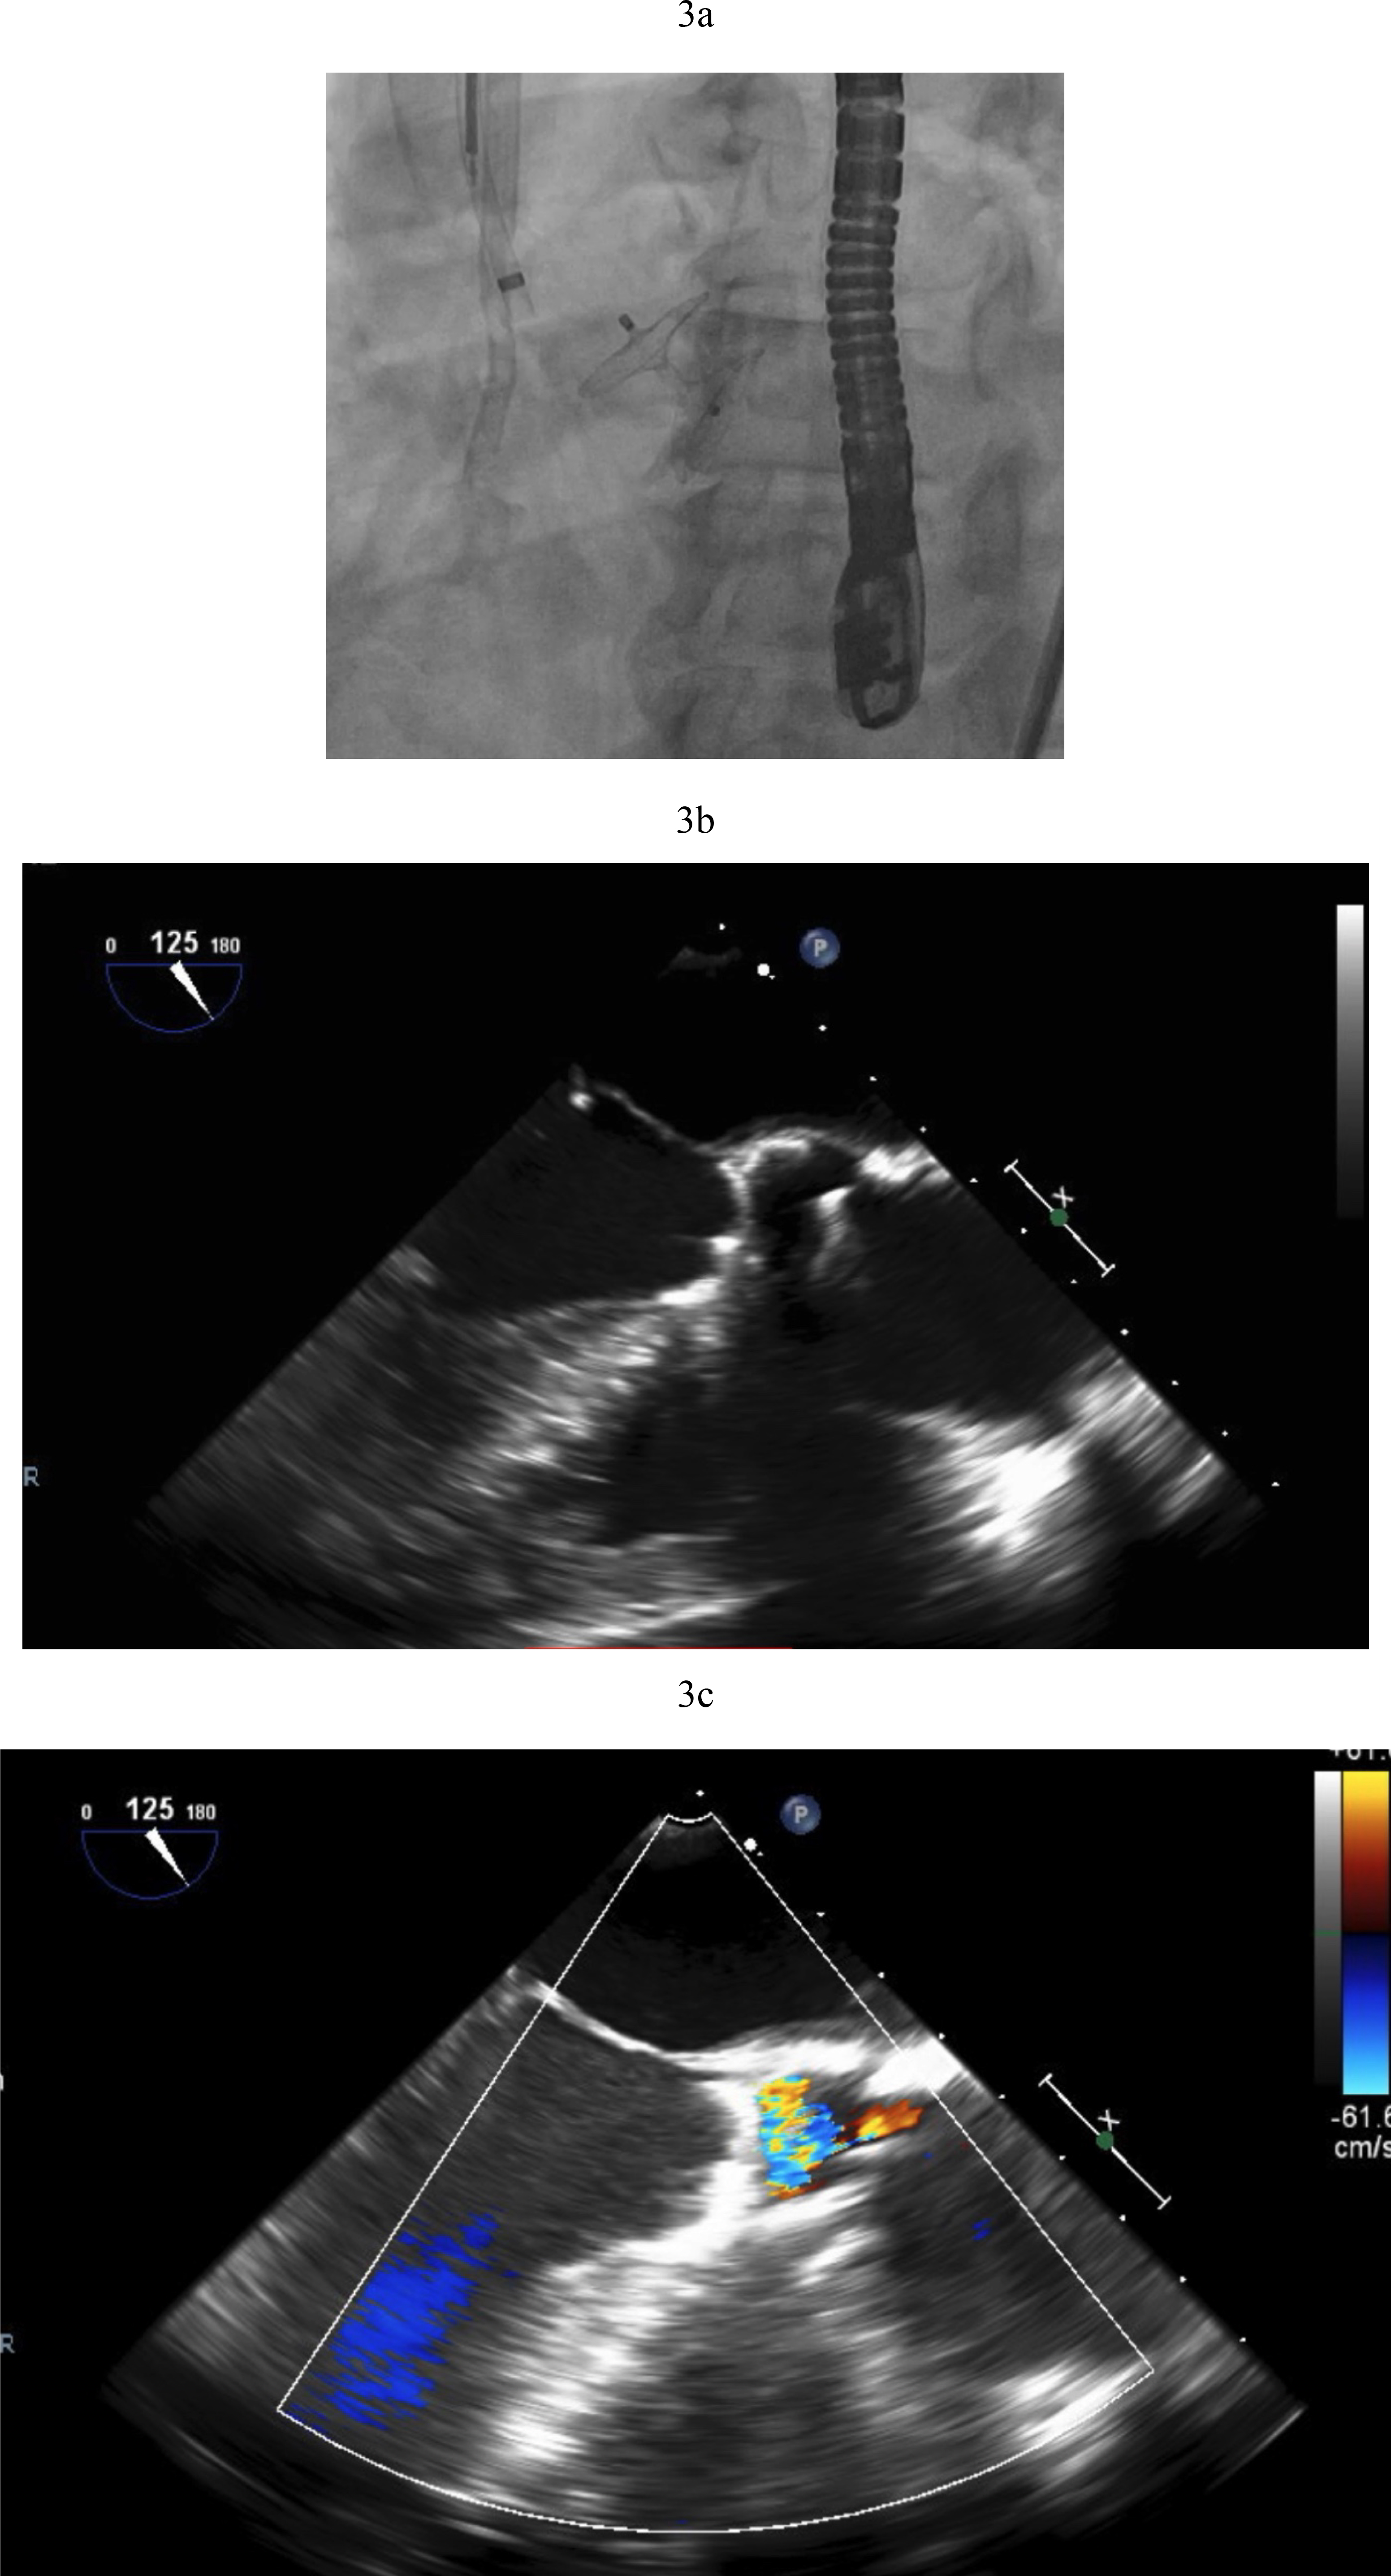

TAVR for AR in patients with LVADs poses additional challenges. The continuous pressure head in the aortic root from LVAD outflow cannula flow increases the risk of ventricular migration. If perivalvular regurgitation is present again the magnitude is magnified by the constant Ao-LV pressure gradient (Fig. 2). The absence of leaflet calcification leads to an increased risk of device misplacement or migration and paravalvular regurgitation from an incomplete seal (Fig. 4a,b). A valve-in-valve strategy in which a second valve is delivered to hold the first valve in place and prevent its migration has been deployed successfully (Fig. 4c). To minimize this risk, LVAD flows should be temporarily decreased during valve deployment. A single center experience which utilized predominantly the self-expanding Evolut TAVR platform reported that 36% of the procedures required a second valve [17]. The French registry of TAVR for native aortic regurgitation noted an 8.8% rate of second valve implantation that portends a worse clinical outcome [18].

Fig. 4. AVR with a self-expanding valve (Medtronic) in LVAD complicated by migration. (a) Medtronic Evolut valve deployed too deep in the ventricle. (b) Evolut valve embolized to the aorta when attempting to reposition the valve with a snare. (c) Second Evolut valve successfully placed across the aortic valve.